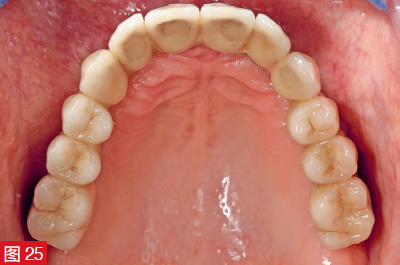

1993 年的聲明 - “在高笑線的情況下,上頜骨的彈性牙齦植入物可以改善美學和言語” - 原則上是正確的。然而,由于未經證實、耐用性差和衛生問題,不再推薦使用牙齦修復體。不僅如此,人們還試圖用粉紅色的瓷粉來完成這部分,以盡可能地模仿自然條件。通過牙冠和牙齦釉質顏色的完美協調,現在可以很好地模仿或再現紅白美學。對于高質量的修復體,最終修復體選擇了分層瓷貼面,而不是人工牙排的形式(圖 20 和 21)。在這種情況下,中間橋體區域設計為橢圓形組織表面形成,然后用復合樹脂嵌體封閉入口(圖 24 和 2<@)。5). 最后,調整動靜咬合。然后用復合樹脂嵌體封閉入口(圖 24 和 2<@)。5). 最后,調整動靜咬合。

圖 25:然后用復合樹脂嵌體封閉螺絲入口。作為替代方案,也可以使用流體樹脂蝕刻進行密封。